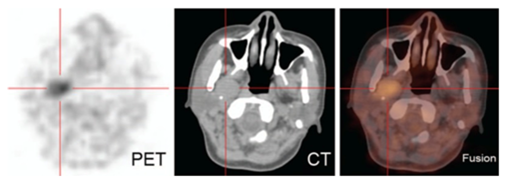

一位41岁的中国女性于2014年11月来到我们的耳鼻喉科门诊,她有2个月的咽异物感觉史。体检发现咽部轻微发红,肿胀、压痛或淋巴结肿大阴性。MRI显示在右PPS中有圆形和明确的肿块,大小为30×20μmm。由于有胃底类癌的病史,经胃镜取出后,建议病人接受18F-脱氧葡萄糖正电子发射断层扫描(18FDG PET)-CT检查,以区分转移性淋巴结与良性淋巴结。PET图像显示18FDG在右侧PPS中摄取增加,与CT上的肿块形状相对应(图7)。没有观察到胃底肿块或增加的摄取。无其他淋巴结、肺或肝转移明显。

图7